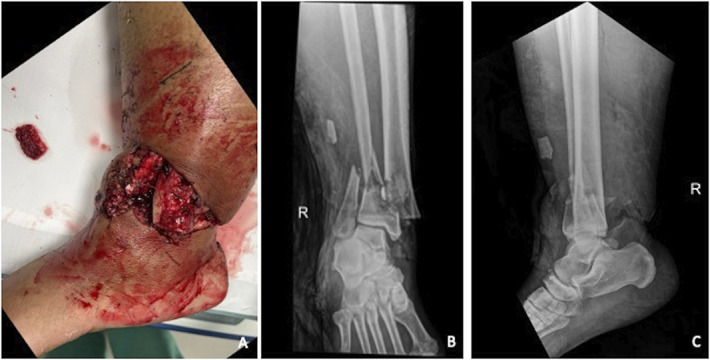

Case: A 42-year-old African-American woman sustained a type IIIA open pilon fracture requiring open reduction internal fixation complicated by wound dehiscence. Acute shortening for primary wound closure was performed followed by relengthening in a circular frame. Owing to the patient's intolerance to the circular frame, pre-existing osseous deformity, large body habitus, and soft tissue compromise, conversion to intramedullary stabilization with standard nailing was deemed exceedingly difficult. We describe the use of a photodynamic bone stabilization system allowing for percutaneous entry and implant flexibility for the purpose of early circular frame removal.

Conclusion: This case demonstrates successful protection of immature regenerate using a photodynamic bone stabilization system, offering another tool to minimize time spent in a circular frame.